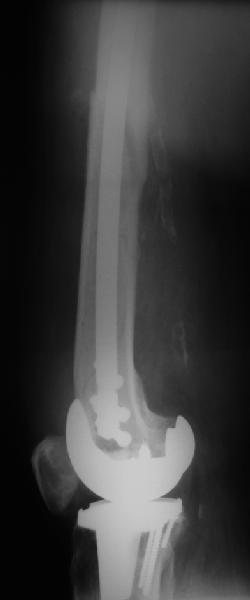

В приложении - недавний перипротезный перелом.